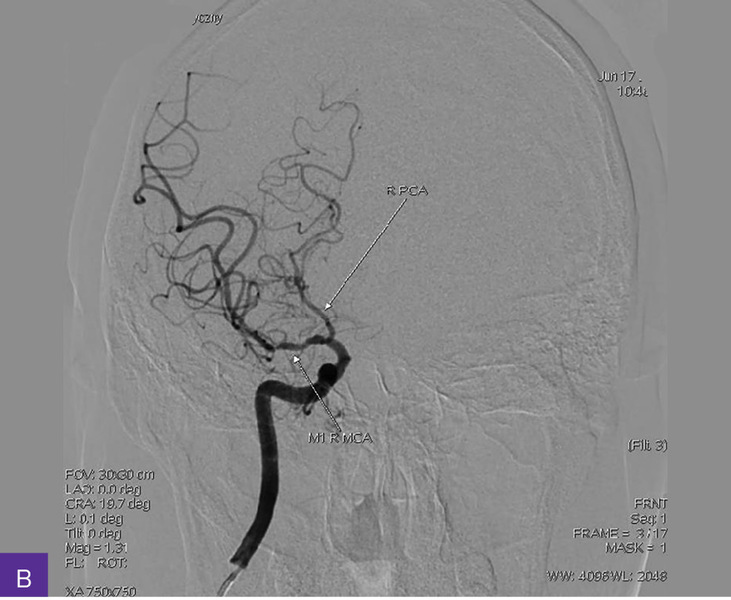

Rycina 4A-C. Cyfrowa angiografia subtrakcyjna (DSA). Widoczna przewlekła niedrożność nadklinowych odcinków obu tętnic szyjnych wewnętrznych, z wzorcem unaczynienia końcowego typu moyamoya, niedrożnością odcinków M1 obu tętnic środkowych mózgu, hipoplazją odcinków A1 obu tętnic przednich mózgu i krążeniem obocznym

Diagnostykę poszerzono o badanie cyfrowej angiografii subtrakcyjnej (DSA – digital subtraction angiography), która uwidoczniła przewlekłą niedrożność nadklinowych odcinków obu tętnic szyjnych wewnętrznych o nieznanej etiologii, z wzorcem unaczynienia końcowego typu moyamoya, niedrożnością odcinków M1 obu tętnic środkowych mózgu, hipoplazją (i/lub zastępczą neoangiogenezą) odcinków A1 obu tętnic przednich mózgu i krążeniem obocznym – głównie przez kolaterale obwodowe obu tętnic tylnych mózgu, po stronie prawej wspomaganym przez napływ z tętnicy oponowej środkowej i ocznej (ryc. 4).